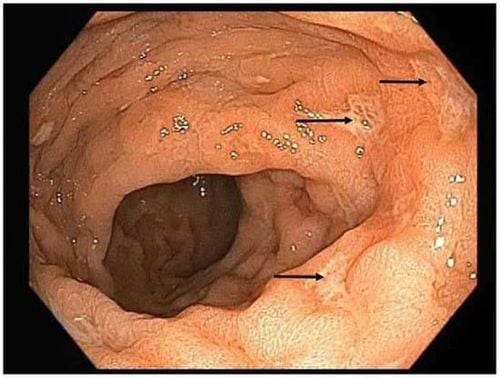

Khám đại tràng trong những trường hợp này thường không phát hiện bất kỳ bất thường nào. Tuy nhiên, khi xét nghiệm mô bệnh học của niêm mạc trực tràng, có thể thấy thâm nhiễm lymphoplasmacytic và bạch cầu trung tính tăng cao trong lớp niêm mạc propia. Các dấu hiệu viêm bao gồm viêm hốc mắt cấp tính, áp xe hốc mắt khu trú, cùng với những vết xói mòn và sự hình thành các u hạt chưa hoàn chỉnh trên hình ảnh nội soi viêm trực tràng (Hình 1).